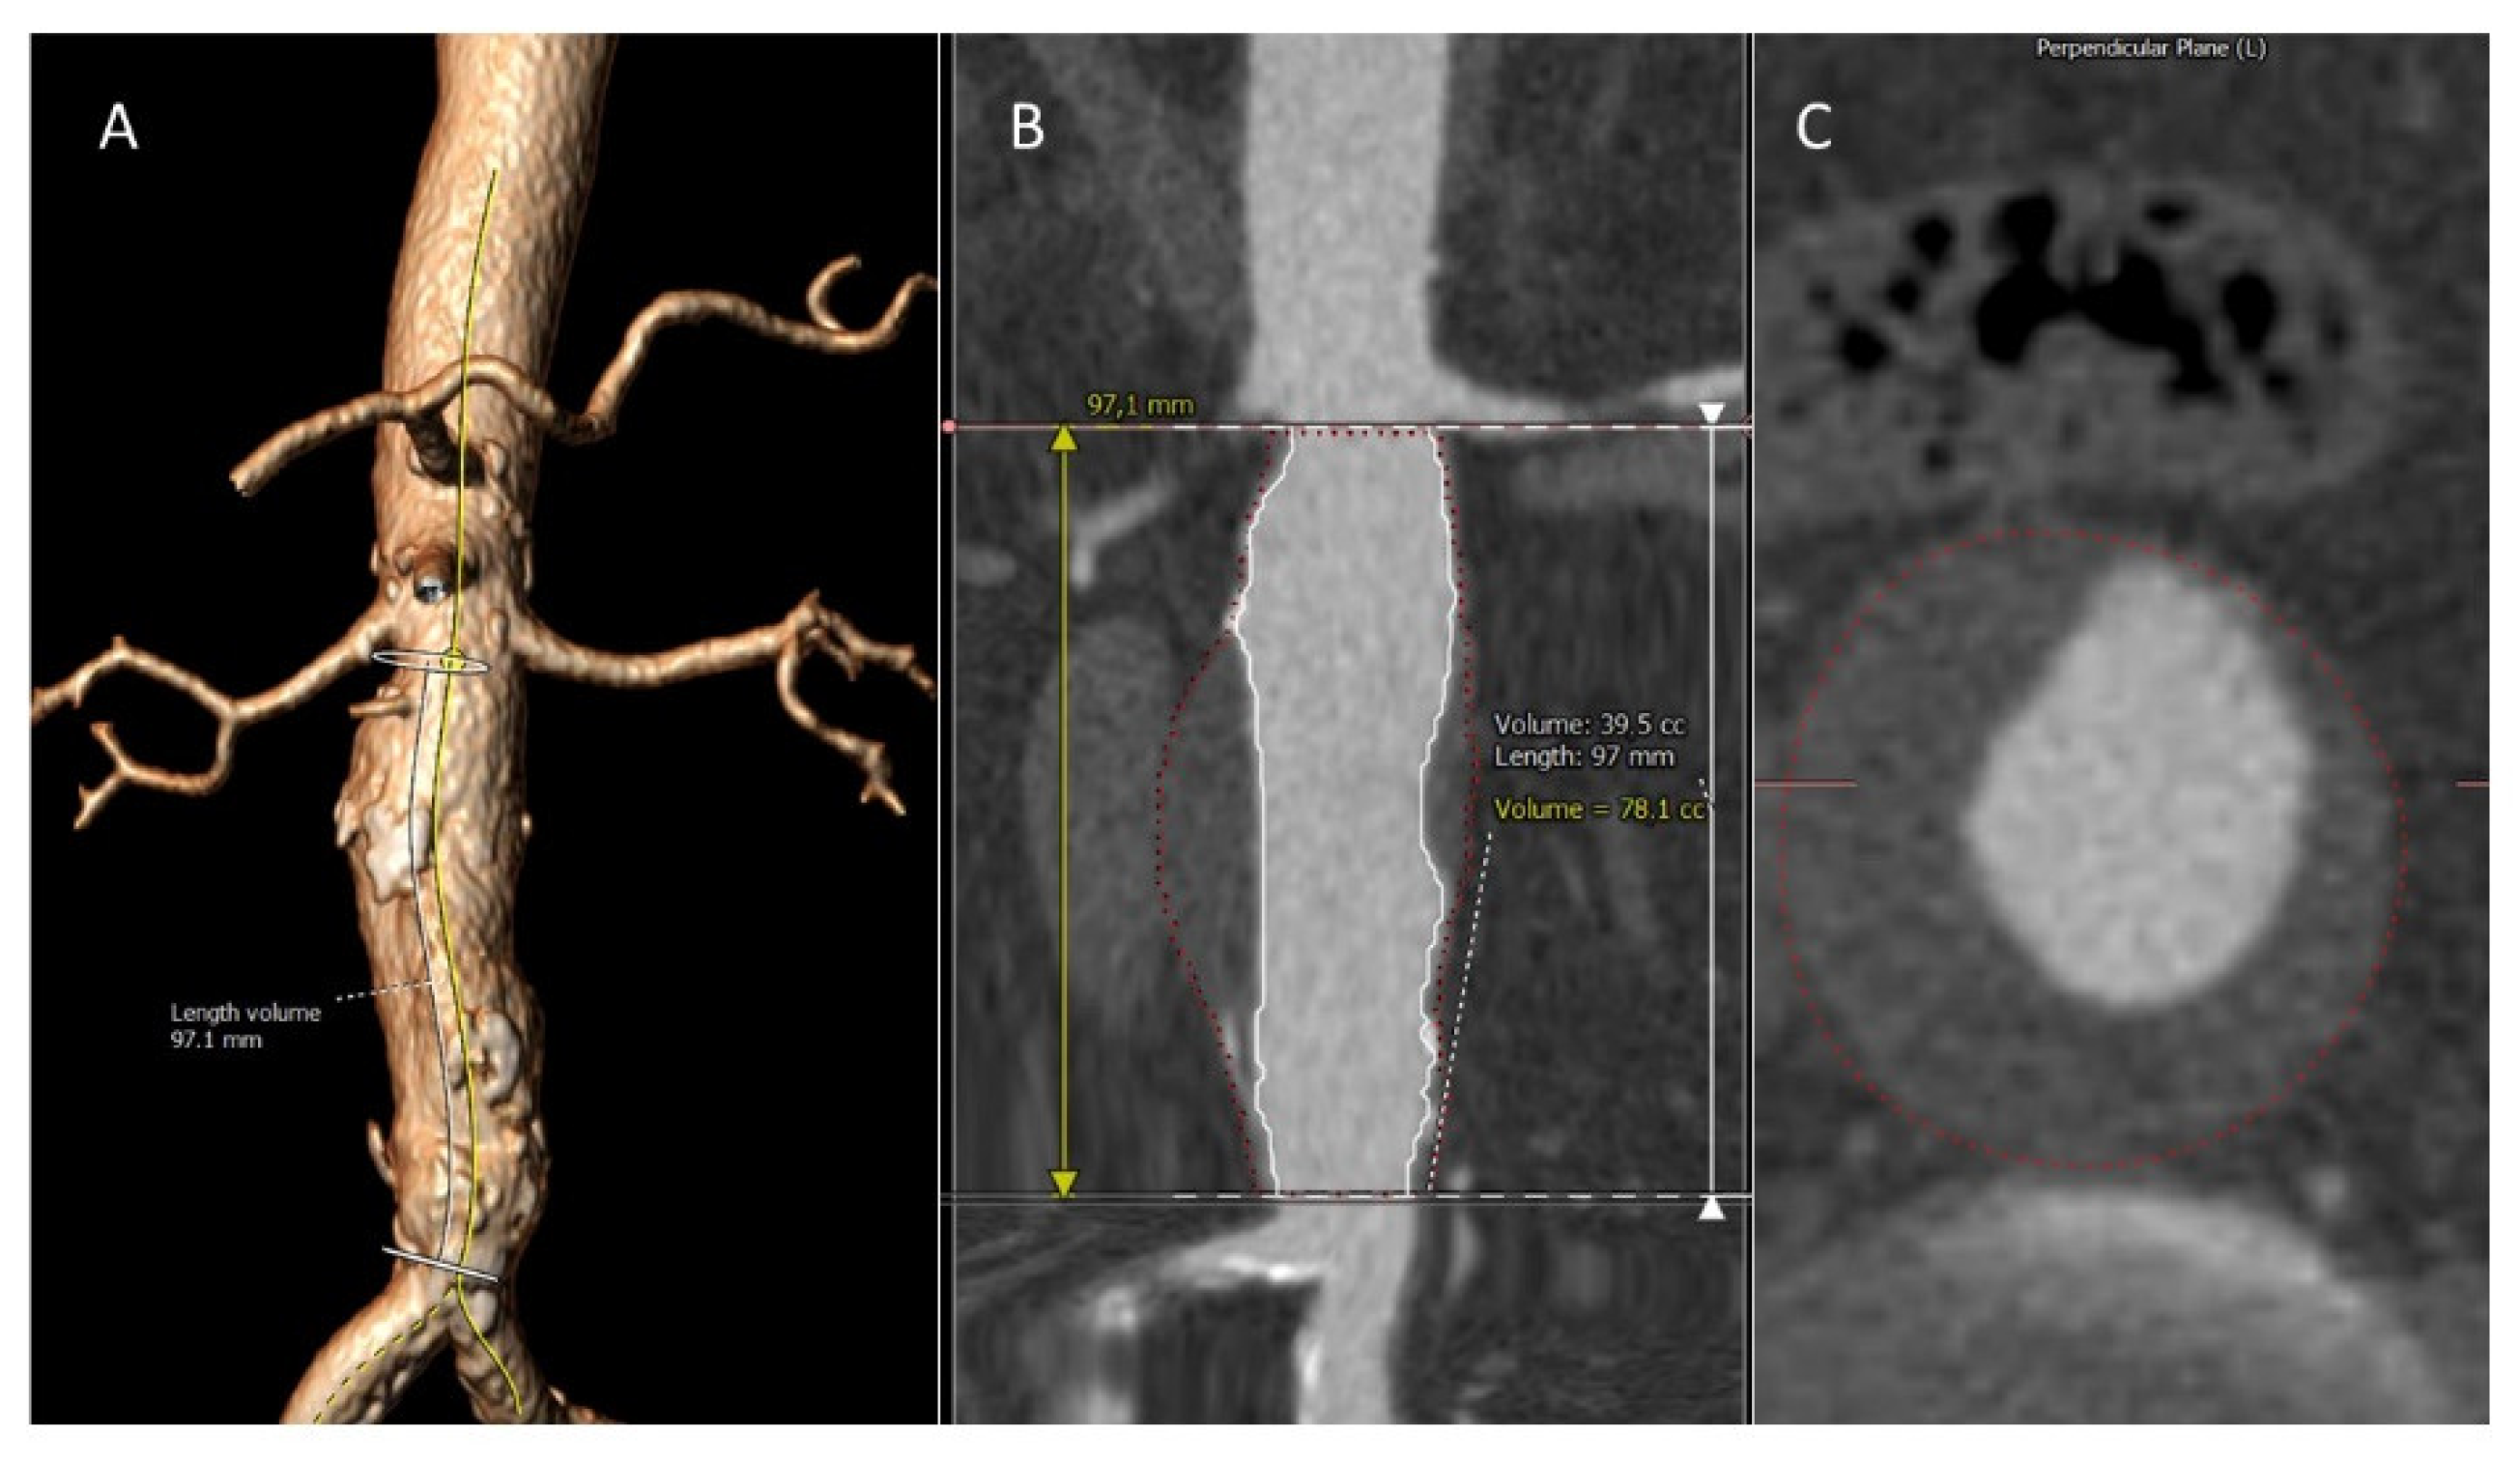

2.3. Image Analysis